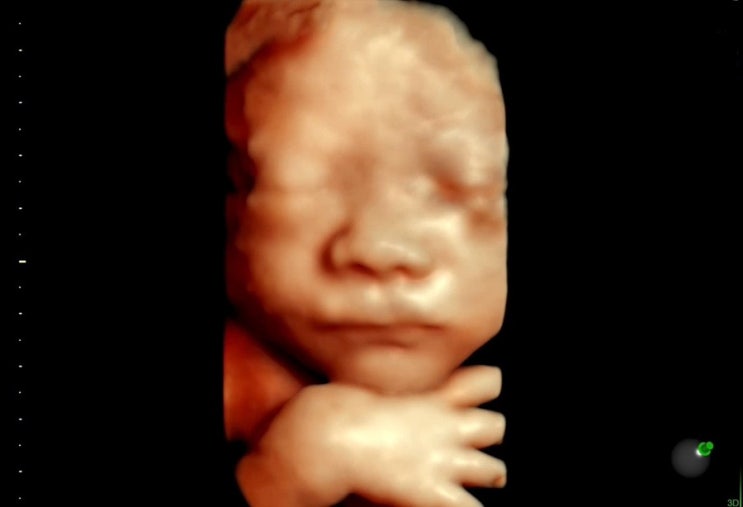

임신 28주차 / 입체초음파 대성공! 너무 귀여운 딱지를 봤다